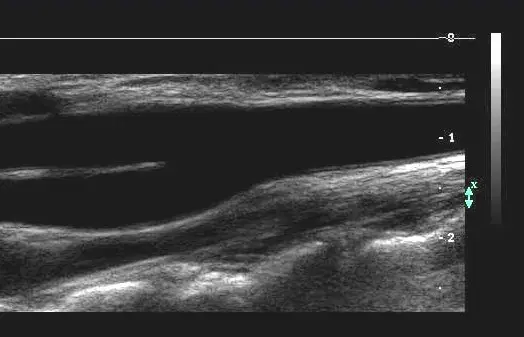

Carotid Ultrasound Case Series: What's the Diagnosis?